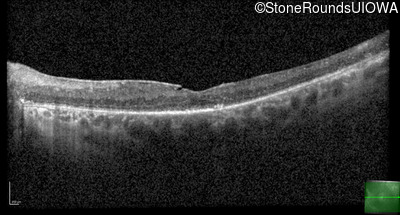

Age at visit: 59 years

OD OS